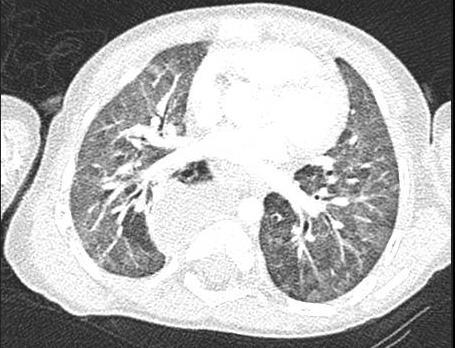

• Patchy bilateral GGO, Consolidations or both

• Peripheral and lower lung zone predominance

• Bilateral & multifocal GGO, +/Consolidations or both

• Halo sign

• Peripheral and subpleural

• Bronchovascular thickening

• Halo sign (Early)